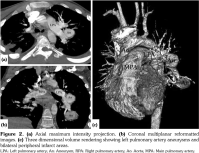

On admission, body temperature was 38.5°C. The patient had tachypnea, dyspnea, tachycardia, decrease of breath sounds in the basal regions of both lungs, and few crackling rales were heard in the left lung field. There was nearly total loss of vision in the right eye and 40% loss of vision in the left eye. Chest radiograph revealed a large left parahilar mass and peripheral infiltration (Figure 1). Computed tomography (CT) angiogram revealed two aneurysmal dilatations originating from the intraparenchymal branches of the left pulmonary artery (18x26 mm, 31x20 mm). Peripheral infarct areas were seen in basal fields of both lungs, and pulmonary embolism was present in the intraparenchymal branches of the right pulmonary artery (Figure 2). Concurrent transthoracic echocardiography showed a tripartite homogeneous hyperechogenic mass with a stalk-like structure, measuring 25x27 mm, filling most of the right ventricle, strongly suggestive of a right ventricular thrombus (Figure 3). The right ventricular pressure was within normal limits, thereby excluding pulmonary hypertension. Doppler ultrasound of lower extremities was unremarkable.